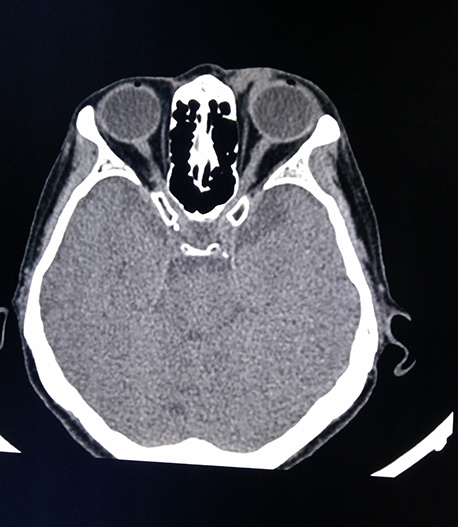

醫(yī)學(xué)影像科現(xiàn)有醫(yī)務(wù)人員15名,其中主任醫(yī)師2名、主治醫(yī)師3名。學(xué)科帶頭人張鐵英主任醫(yī)師、教授,曾任舟山市醫(yī)學(xué)會(huì)放射學(xué)分會(huì)主委,應(yīng)用影像新技術(shù)對(duì)人體各系統(tǒng)進(jìn)行檢查及疾病診斷,尤其是對(duì)神經(jīng)系統(tǒng)、呼吸系統(tǒng)、消化系統(tǒng)、骨關(guān)節(jié)及肌肉系統(tǒng)疾病的影像診斷有較高造詣。醫(yī)學(xué)影像科7×24小時(shí)開(kāi)放,為醫(yī)院門(mén)診、急診及住院患者提供優(yōu)質(zhì)、高效、迅速的影像診療服務(wù)。